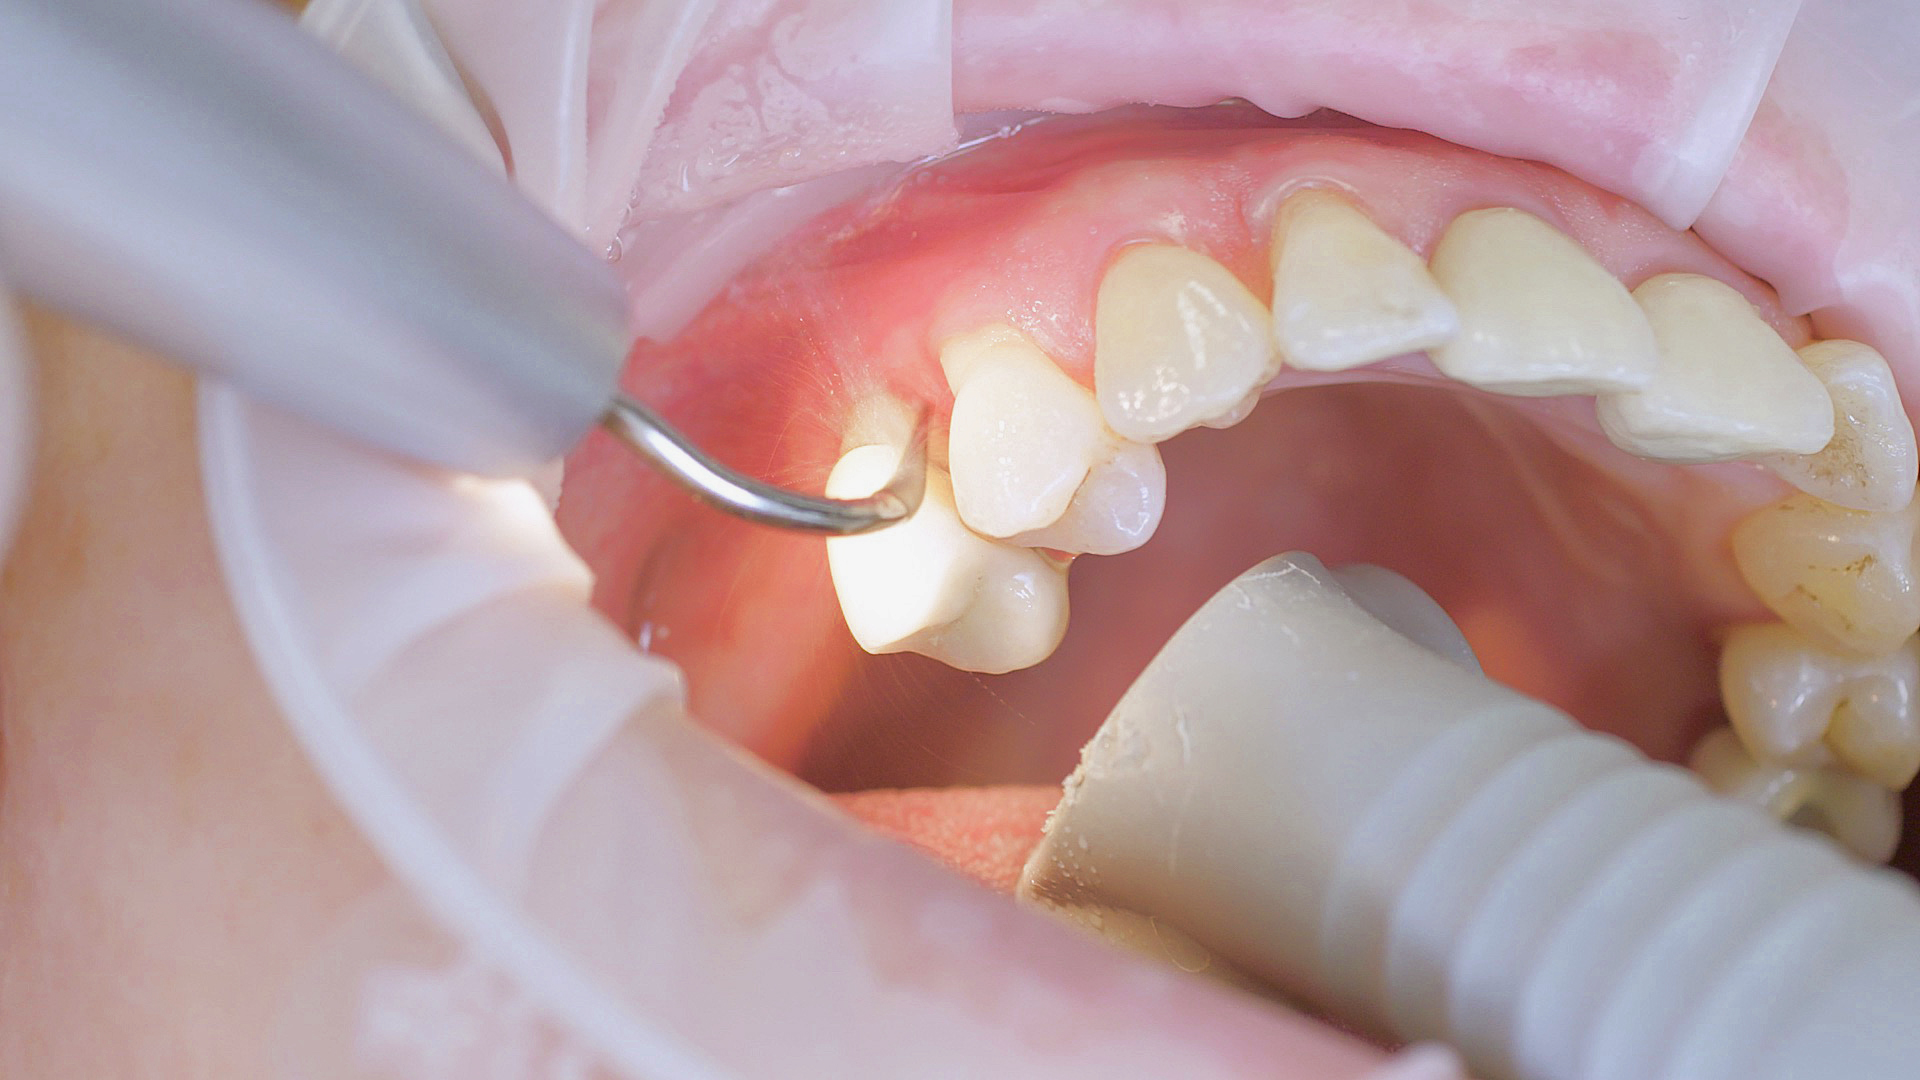

Healthy peri-implant tissue does not show any signs of redness, swelling or bleeding, neither does it secrete pus when probed.[5] Based on the consensus document, Prof. Giovanni Salvi explained the importance of regu- lar probing — preferably with a flexible probe, as implant components often tend to obstruct the procedure.[5] In the case of mucositis or initial peri-implantitis already being present, the non-surgical removal of hard deposits and biofilm should be attempted first. For this purpose, ultra- sonic power and special instruments designed to protect the implant should be employed (Fig. 3; piezo scaler Tigon+ with 1I, W&H). In case of no remission, the recall frequency needs to be increased. However, specific recommendations, applicable to individual cases, are not yet available in this context.[15]

Fig. 3: Implants and superstructures can be successfully cleaned with ultrasonic devices and special plastic instruments during postoperative care or non-surgical therapy.